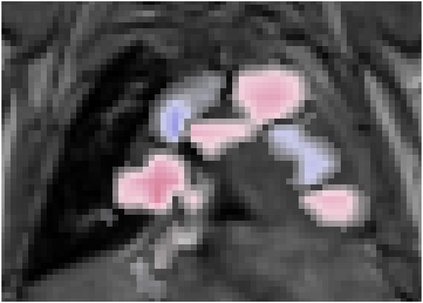

Various imaging modalities allow for time-dependent image reconstructions from measurements where its acquisition also has a time-dependent nature. Magnetic particle imaging (MPI) falls into this class of imaging modalities and it thus also provides a dynamic inverse problem. Without proper consideration of the dynamic behavior, motion artifacts in the reconstruction become an issue. More sophisticated methods need to be developed and applied to the reconstruction of the time-dependent sequences of images. In this context, we investigate the incorporation of motion priors in terms of certain flow-parameter-dependent PDEs in the reconstruction process of time-dependent 3D images in magnetic particle imaging. The present work comprises the method development for a general 3D+time setting for time-dependent linear forward operators, analytical investigation of necessary properties in the MPI forward operator, modeling aspects in dynamic MPI, and extensive numerical experiments on 3D+time imaging including simulated data as well as measurements from a rotation phantom and in-vivo data from a mouse.